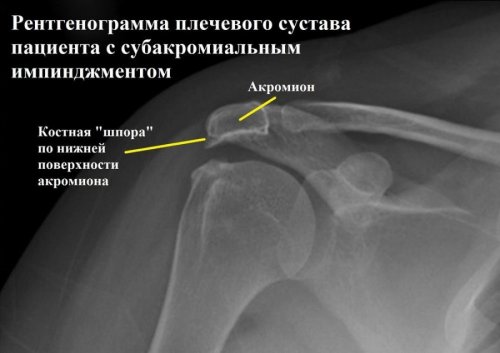

Например, при наличии костной шпоры происходит уменьшение субакромиального пространства и наблюдается повреждение вращательной манжеты.

• На третьем этапе ИС можно наблюдать костные шпоры, а также разрыв манжеты. Встречается у пациентов старше 40 лет. К сожалению, прогноз на полнейшее выздоровление практически отсутствует, так как основным методом лечения является хирургическое вмешательство.

В обязательном порядке стоит пройти рентгенологическое обследование, для определения структуры и строения акромиально-ключичного сочленения и уточнения формы акромиона. Если врач подозревает разрыв сухожилия вращательной манжеты, то рекомендуется пройти магнитно-резонансную томографию. МРТ позволяет получить максимально точную картинку патологического процесса, для этого применяют влияние магнитных волн.